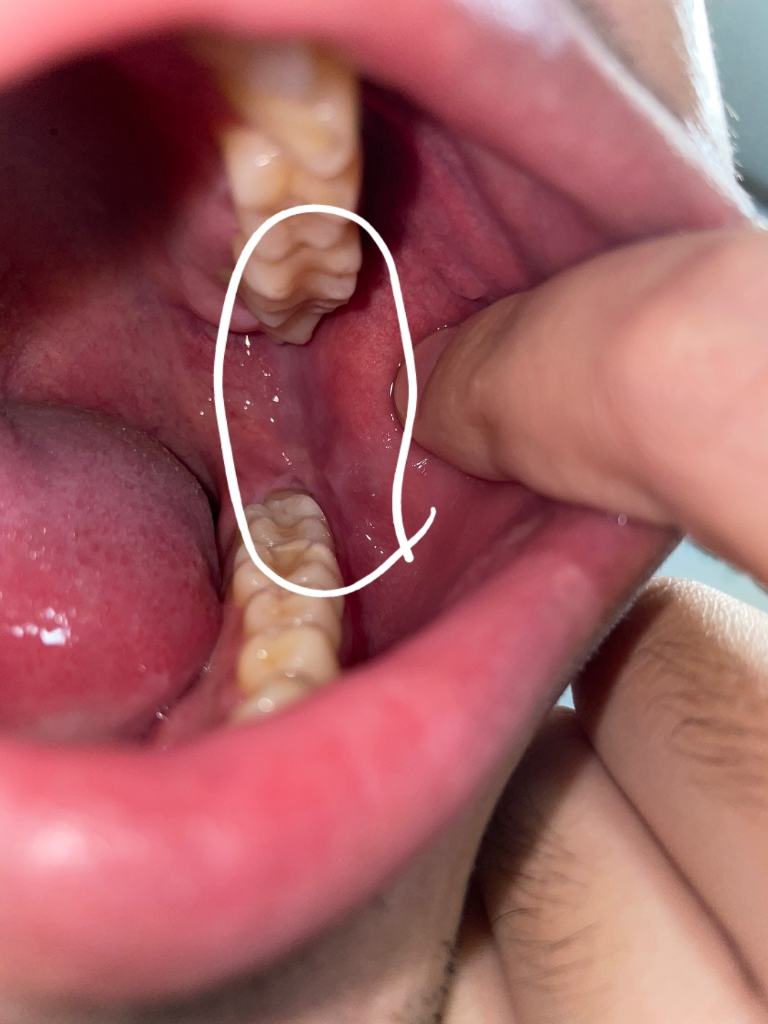

입안을 보던중 양쪽 어금니 안쪽 위치에 사진과 같이 하얀색 (연한 핑크?) 세로줄이 보여서 질문드립니다. 혹시 백반증인가 그건가요..? 양쪽에 있긴한데 한쪽이 조금더 넓게 보입니다 통증은 없어요

• 1번 째 사진